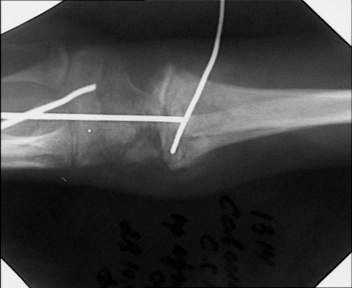

Прооперировали. Провели откытую репозицию , фиксацию спицами, иммобилизация гипсовой повязкой.

НСО г Куйбышев ЦРБ

Зырянов Сергей

Кликните для загрузки файла 28 10 03 _.jpg